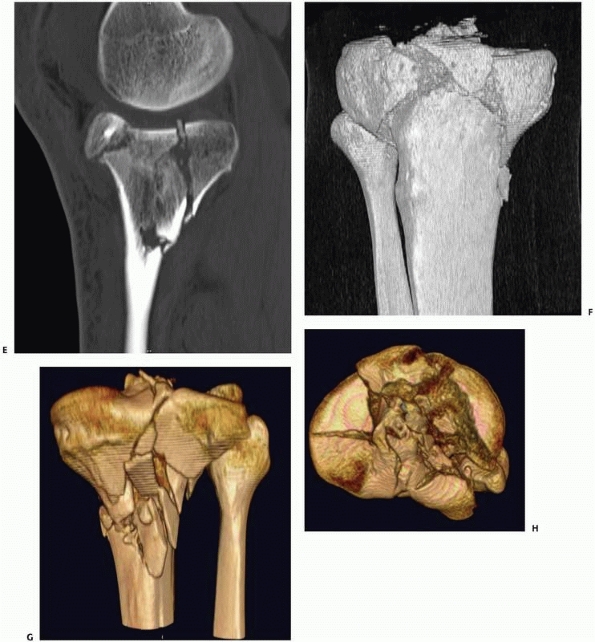

FIGURE 16-3 A, B.

Anteroposterior and lateral views of a complex bicondylar tibial plateau fracture taken after the limb was placed in a spanning external fixator. Axial computed tomography (CT) (C) and two-dimensional reconstructions in the coronal (D) and sagittal (continues) |

FIGURE 16-3 (continued) (E) planes better demonstrate the extent of comminution. With high-resolution three-dimensional reconstruction (F, G),

a very good appreciation of the fracture pattern is possible. Finally, the tibial plateau can be viewed from “above” by digitally subtracting the femur and patella and rotating the image (H). For complex fractures such as this, advanced CT scanning is unparalleled. |